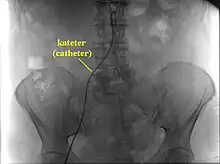

Cateterismo cardíaco, Cinecoronariografia, Angiografia Coronária ou Estudo Hemodinâmico é um exame invasivo para examinar vasos sanguíneos e o interior do coração. O acesso ao interior do coração é feito através de um tubo longo, fino e flexível, chamado cateter, geralmente com cerca de 2,5 milímetros de diâmetro e 1 metro de comprimento, colocado por um vaso sanguíneo periférico do braço, da coxa ou do pescoço. Tem como objetivo corrigir problemas em veias e artérias, como obstruções.[1]

Algumas vezes uma substância contrastadora (ou simplesmente contraste) especial é colocada no cateter para fazer com que o interior do coração e vasos sanguíneos apareçam nos raios-x. O contraste pode mostrar se placas ateroscleróticas estreitaram ou bloquearam as artérias coronárias. A aterosclerose é uma doença caracterizada pela formação de placas de gordura no interior de um vaso sanguíneo, que estreitam a passagem no interior desse vaso, podendo bloquear o fluxo de sangue ao coração. Bloqueios nas artérias também podem ser vistos usando ultrassom durante o cateterismo cardíaco. Ultrassom usa ondas sonoras para criar imagens detalhadas dos vasos sanguíneos do coração.